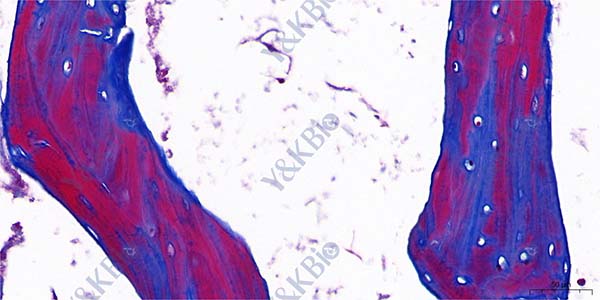

以往的Masson三色染色多用于显示结缔组织中各种纤维成分,如果采用Masson三色染色的方法,对骨受损后处于不同修复时期的骨组织进行染色,镜检观察,并用计算机多功能图像分析系统进行分析,结果显示不同修复时期骨基质中胶原纤维均呈红-蓝相间,骨修复早期红染少,蓝染多,随着修复时间的延长红染区域增多。在染色程序及试剂都一致的情况下,染色反应的颜色决定于组织的成分。

骨中胶原主要是I型胶原,成熟骨吉林Masson染色胶原着鲜红色,在新生骨走向成熟过程中表现为红-蓝相间现象,表明骨组织中胶原的成熟程度影响Masson的染色反应,可以用Masson染色来评价骨质的成熟程度,新生骨质红染少,成熟骨内红染多,即骨质越成熟,红染越多。同样也可以用此染色观察骨细胞和成骨细胞的活动状况,在细胞周围出现的蓝染胶原系新生部分,细胞周围蓝染区域的大小代表细胞的新近活动程度。

Masson 染色骨损伤后早期红染区域较少,骨细胞及成骨细胞周围的蓝色着染区域较大,随着修复时间的延长,可见骨组织红染区域面积占测量区面积的百分数逐渐增大,表明成熟骨组织在逐渐增多,这与其他指标的结果一致。

采用Masson三色染色的方法,对骨受损后处于不同修复时期的骨组织进行染色,操作方法简单,普通脱钙骨切片即可,在新生骨走向成熟过程中表现为红-蓝相间现象,新生骨质红染少,成熟骨内红染多,即骨质越成熟,红染越多,结合计算机图像分析处理系统可定量分析骨组织的成熟程度。